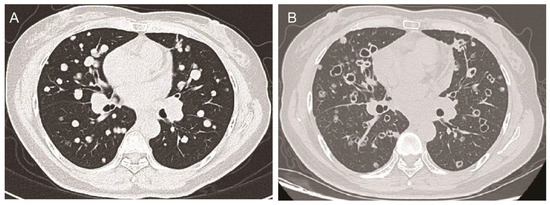

Tumor Cavitation with Anlotinib Treatment in Lung Adenocarcinoma

Tumor cavitation is distinguished by the emergence of central necrosis and cavity formation within the tumor mass, which indicates a notable outcome of anti-angiogenic therapies. This case describes a 52-year-old Chinese female with advanced EGFR-mutated lung adenocarcinoma (Exon 19 deletion), which was metastatic to bilateral lungs, brain, and right adrenal gland, who exhibited a radiographic response to combination therapy with the third-generation EGFR tyrosine kinase inhibitor (TKI) aumolertinib and the anti-angiogenic agent anlotinib. The patient achieved near-complete cavitation of almost all bilateral lung nodules, manifesting as distinctive “bullet hole” lesions on the chest CT. Despite this initial response, disease progression occurred two months later with new liver metastases, culminating in the patient’s death. This case underscores the potential efficacy of EGFR TKIs and anti-angiogenic agents in inducing unique tumor microenvironment modifications, while highlighting the transient nature of such responses and the critical need to address resistance mechanisms. Tumor cavitation may serve as a radiographic marker of anti-angiogenic activity but does not preclude metastatic spread, necessitating vigilant monitoring even in the setting of favorable imaging changes. Full article